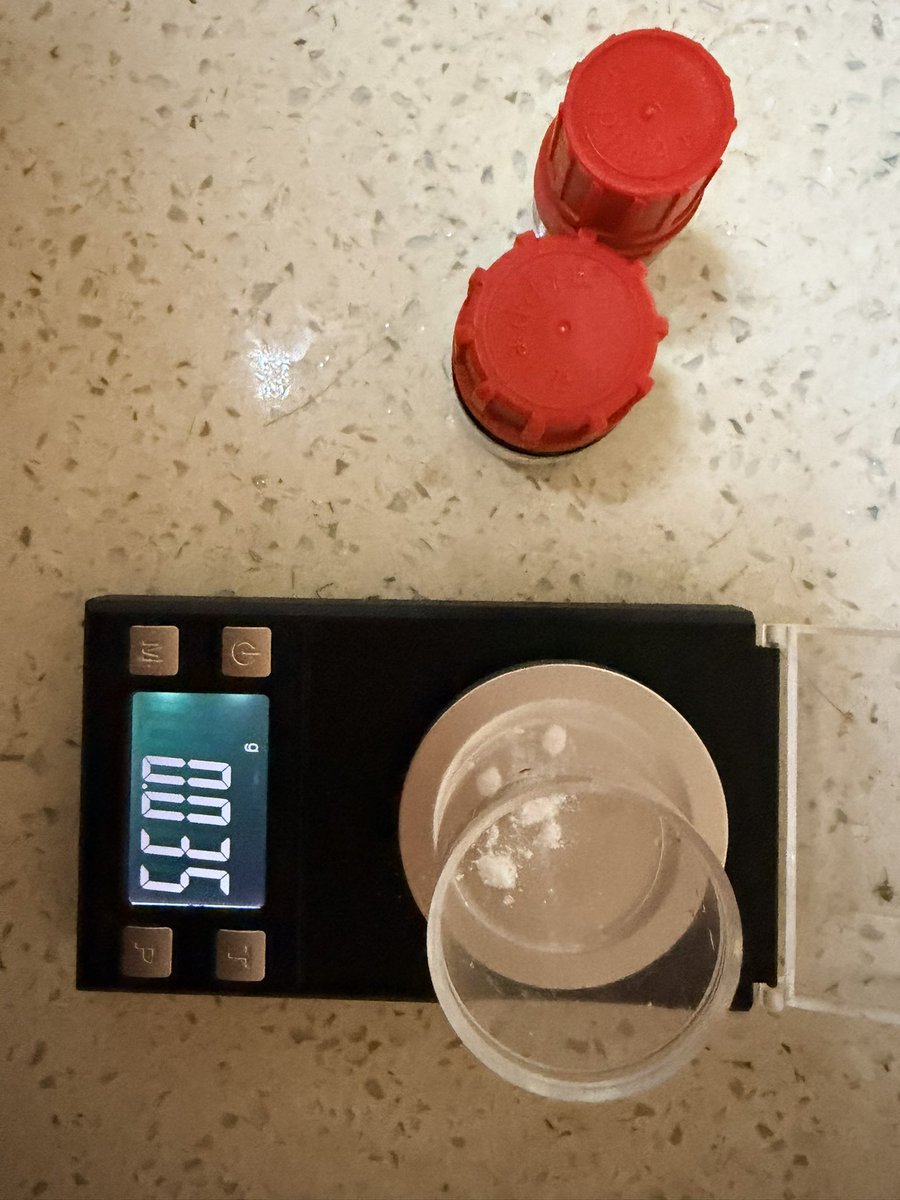

对于药物过量引起的中枢神经系统副作用,有一些不常见或常见的药物来控制症状。

评论区欢迎补充 https://t.co/7S4tGVDEM5